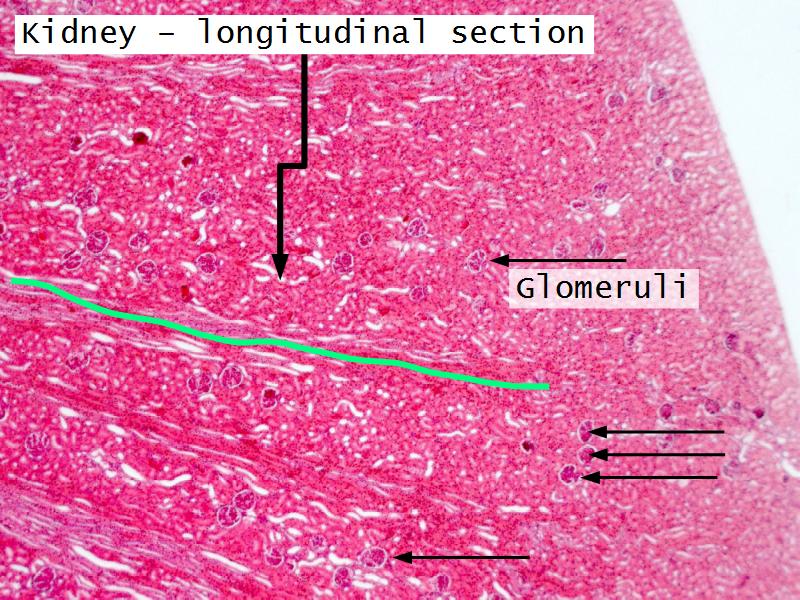

- Slide 76: Kidney